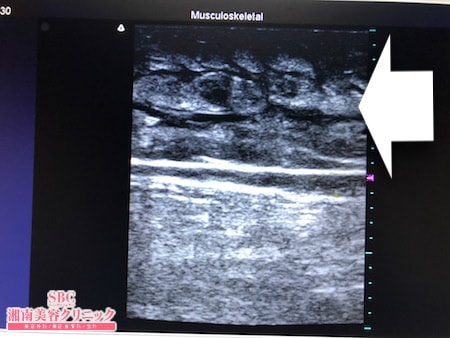

No.252668【脂肪吸引】何をやっても脚が細くならなかったので脂肪吸引で太ももを確実に細くする!左太もも前面術中タッチビュー

その術中変化を紹介しましょう。

取れる皮下脂肪は根こそいでおきましたので

患者様は今回の脂肪吸引で

念願の細い脚を手に入れることでしょう。